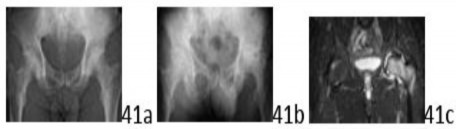

3. # 41a 41b 41c A 61-year-old man who reports left hip pain is seen in the emergency department. Figure 41a shows a radiograph obtained at that time. Ten months later, he reports excruciating left hip pain with ambulation. He notes that the pain has markedly worsened over the past several weeks. Figures 41b and 41c show a current radiograph and a coronal inversion recovery MRI scan of the pelvis. What is the most likely diagnosis?

1. # Infection of the hip

2. # Fracture of the hip

3. # Osteoarthritis of the hip

4. # Osteonecrosis of the hip

5. # Rheumatoid arthritis of the hip

DISCUSSION: The initial radiograph shows subtle flattening of the left femoral head, suggestive of osteonecrosis but without significant subchondral sclerosis. Figure 41b shows marked collapse in the left head over the intervening 10 months, and the MRI scan reveals collapse, significant edema in the head, and low signal intensity in the superior segment, all suggestive of osteonecrosis. Note that the right hip shows MRI changes, suggesting bilateral disease in this patient. The Preferred Response to Question # 41 is 4.